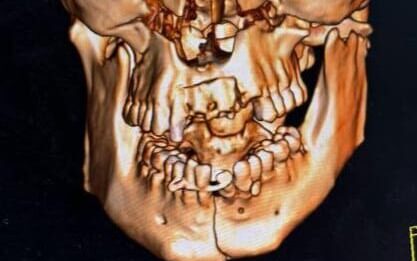

Orthognathic Surgery

Orthognathic surgery corrects jaw and lower face structure, growth, and airway issues like sleep apnea and TMJ disorders , malocclusionproblems due to skeletal disharmonies.